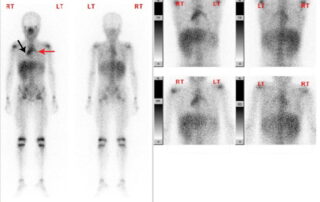

Ολόσωμο σπινθηρογράφημα με Γάλλιο-67 (Gallium-67)

Απεικόνιση με Γάλλιο-67 Το πρώτο ραδιοφάρμακο που χρησιμοποιήθηκε και χρησιμοποιείται έως σήμερα ευρέως για την απεικόνιση όγκων [...]